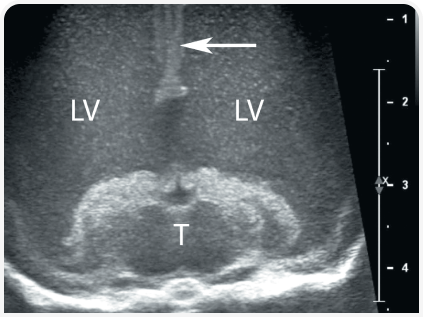

Практичным методом визуализации боковых желудочков является ультразвуковое исследование через открытый родничок.